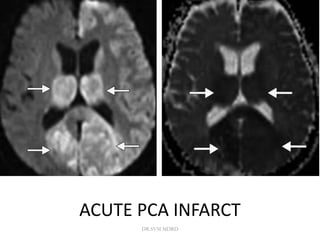

ACUTE PCA INFARCT